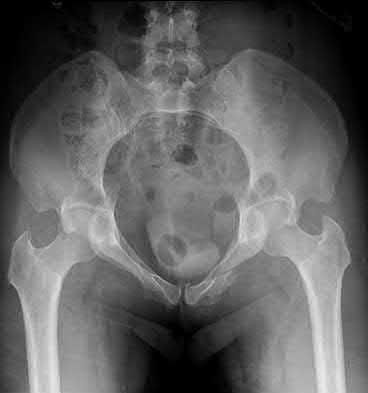

3. # Which of the following is not an appropriate implant for treatment of the fracture seen in Figure A?

5. Sliding hip screw Corrent answer: 5

The image shows a reverse obliquity intertrochanteric hip fracture.

According to the referenced article by Haidukewych et al, unstable peritrochanteric hip fractures have a worse outcome (failed in 9/16 cases) if treated with a sliding hip screw. Two additional factors that were found to have a strong correlation with postoperative failure (nonunion, loss of reduction) were poor reduction and poor implant placement. In this study, fixed angle devices were superior. Intramedullary fixation has the added advantage of a shorter lever arm and less potential for fracture collapse and limb shortening.

The IMN also acts as a medial buttress.

According to Sanders et al, the dynamic condylar screw (DCS) can also be used in subtrochanteric models, but should not be used if extensive comminution is seen, as they reported a high failure rate with DCS in these fractures if highly comminuted. They report a 77% overall union rate with this device.